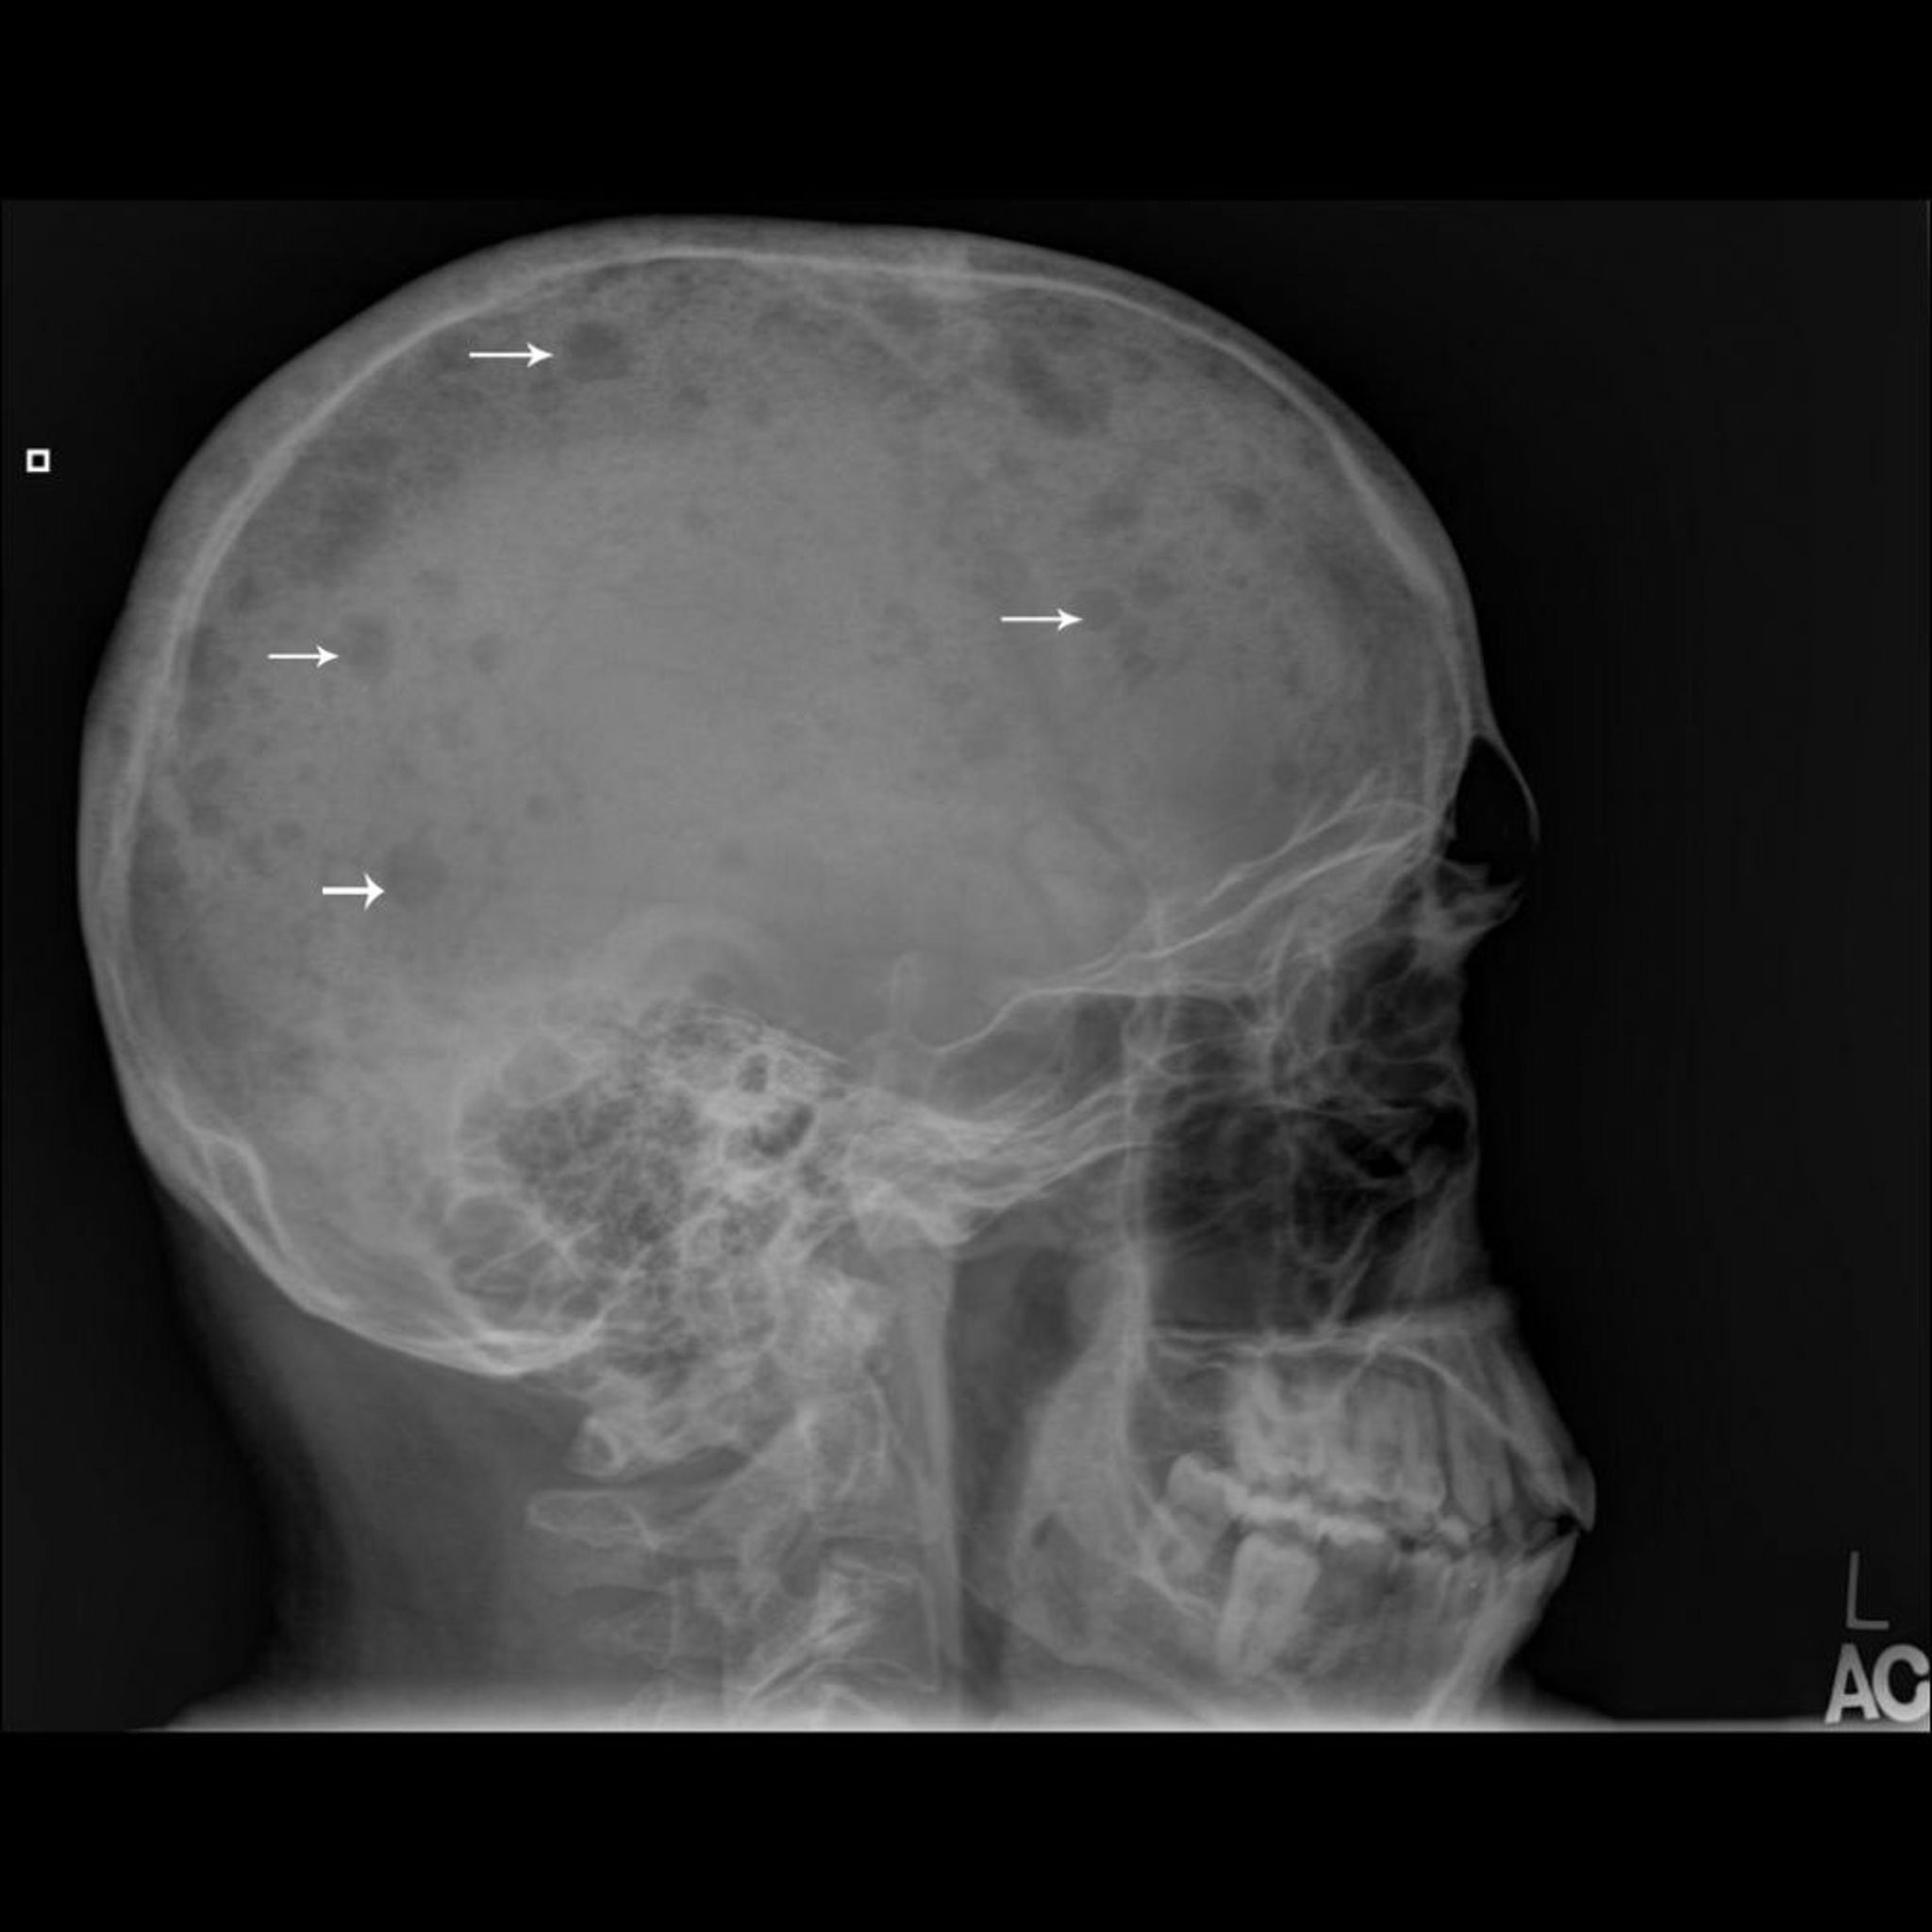

تُظهر هذه الصورة الشعاعية للجمجمة مواضع متعددة مثقوبة في العظم (اتجاه الأسهم)، وهو مظهر نمطي للورم النقوي المتعدد.

جرى استخدام الصورة بعد موافقة أصحابها Michael J.Joyce, MD, and Hakan Ilaslan, MD.